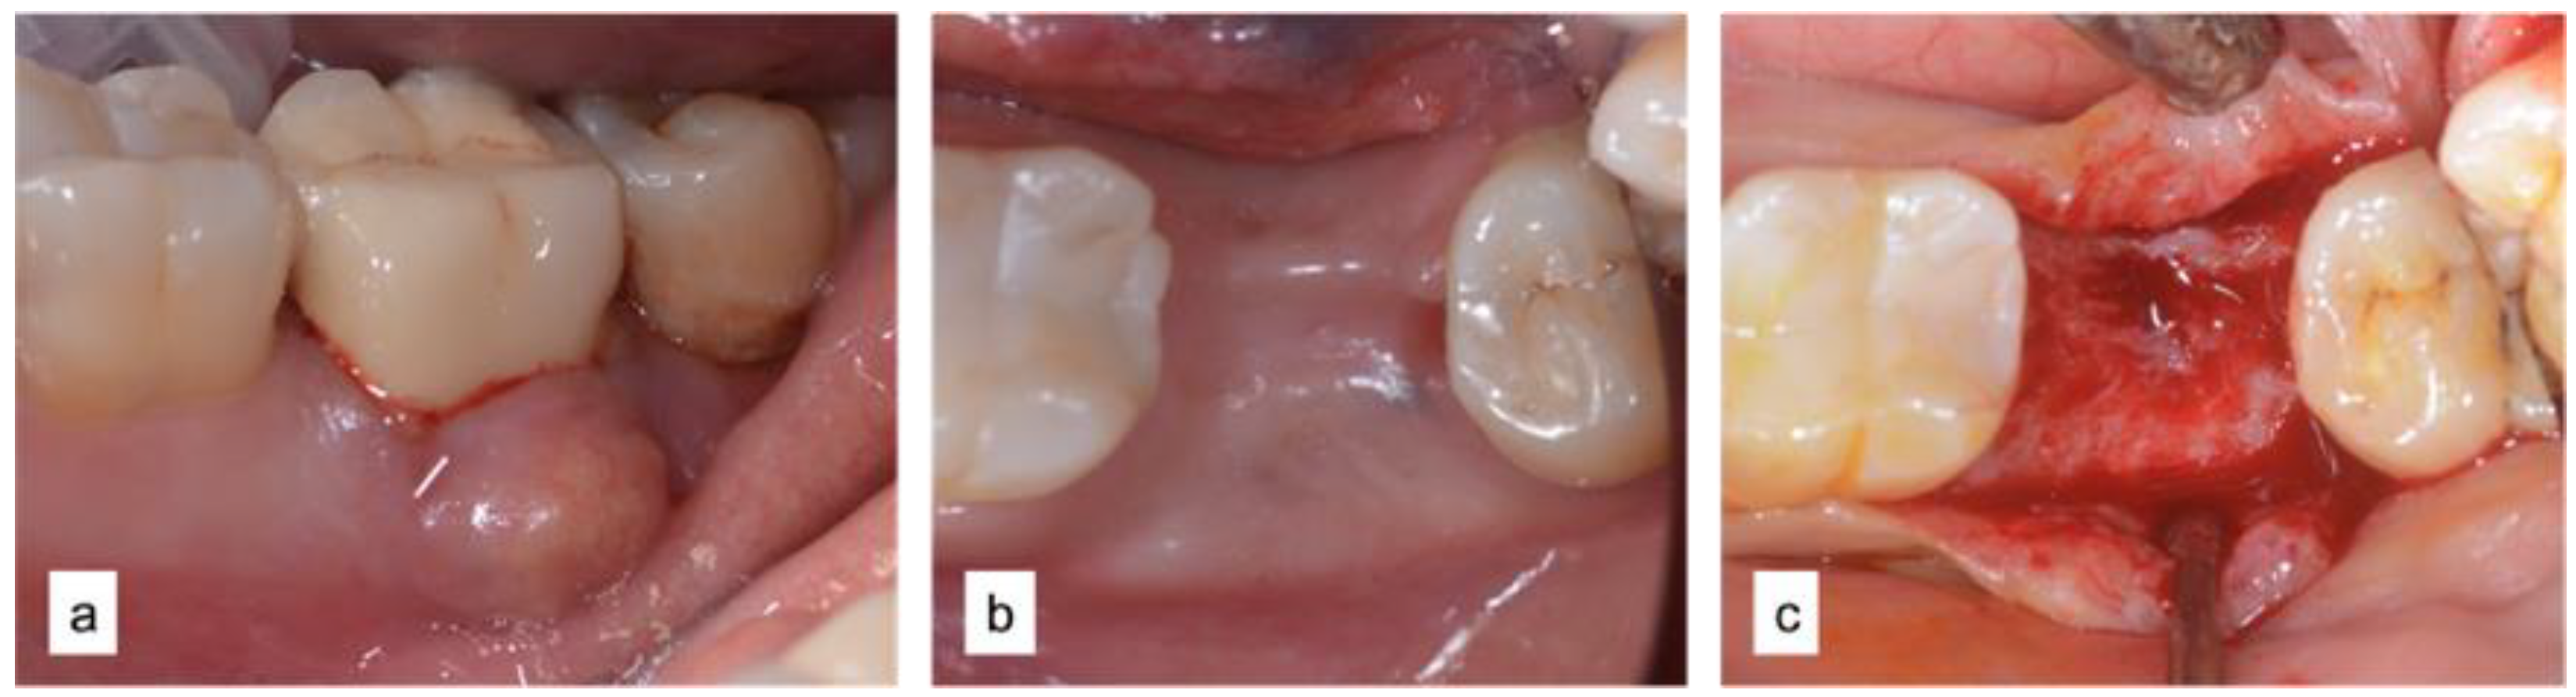

2.2.1. Case 1—MPI Technique Zone 47